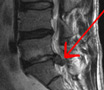

Nikamavälilevyt sijaitsevat selkänikamien väleissä. Välilevyt toimivat selkärangan iskunvaimentimina ja lisäävät sen notkeutta. Välilevy koostuu syykehästä ja sen sisällä olevasta pehmeästä ytimestä. Välilevyn pullistumassa välilevyn geelimäinen sisäosa työntyy ulospäin sitä ympäröivän syykehän läpi. Pullistuma voi tapahtua esimerkiksi kuormittaessa selkää painonnoston yhteydessä.